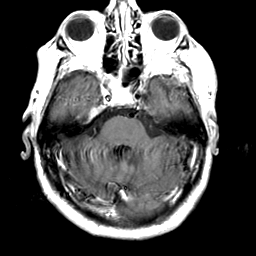

Meningioma, MR Study #2 -- Slice #5

[Home][Help][Clinical] Slice 5